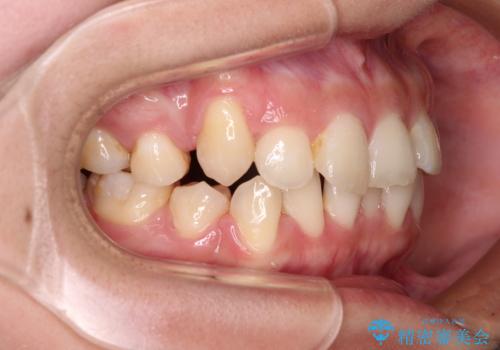

八重歯の抜歯矯正 補助装置とワイヤーを併用したインビザライン矯正治療

- 八重歯と上顎正中のズレを気にして来院された患者様です。

インビザラインによる矯正治療を希望されたため、八重歯改善のための抜歯矯正部分や上顎正中の大幅に位置移動は、補助装置やワイヤー矯正を併用し、その後はインビザラインにて行うこととしました。

ワイヤー矯正単体の方が期間や仕上がりは優位であるとご説明しましたが、インビザラインでの治療を希望されたため、補助装置併用の矯正治療を行うこととしました。